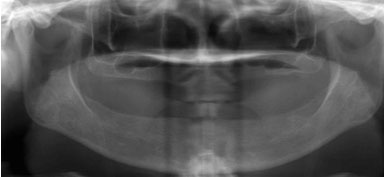

不翻瓣、3-4mm

微孔植入

数字化3D导板定位植体深度、角度,微孔植入创口牙根大小

骨量严重萎缩的情况下,利用斜行植体等技术,避免植骨手术。